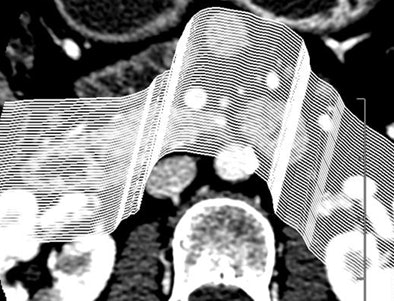

Certainly imaging-based diagnosis of the cysts has its limitations. For one thing, MDCT can diagnose six different pancreatic lesion types, including side branch intraductal papillary mucinous neoplasms (IPMNs), serous microcystic adenomas, epithelial cysts, mucinous cystic neoplasms, lymphatic cysts, and cystic islet cell tumors. But it can't always tell them apart.

Some lesion types look the same at CT, with overlapping appearance occurring, for example, between a mucinous cystic neoplasm and a thin-walled simple cyst that has no risk of malignancy. And mucinous cystic neoplasms are indistinguishable from benign epithelial cysts.

Worrisome features for malignancy are solid tissue within the cyst, obstruction of the main pancreatic duct ≥ 1 cm or the common bile duct, regional lymphadenopathy, or interval enlargement of a lesion, Jeffrey said.

Small cystic lesions not worrisome for malignancy under 3 cm include side branch IPMNs, and serous microcystic adenomas, which are easily characterized by their honeycomb matrix that is also easily seen on ultrasound, Jeffrey said.